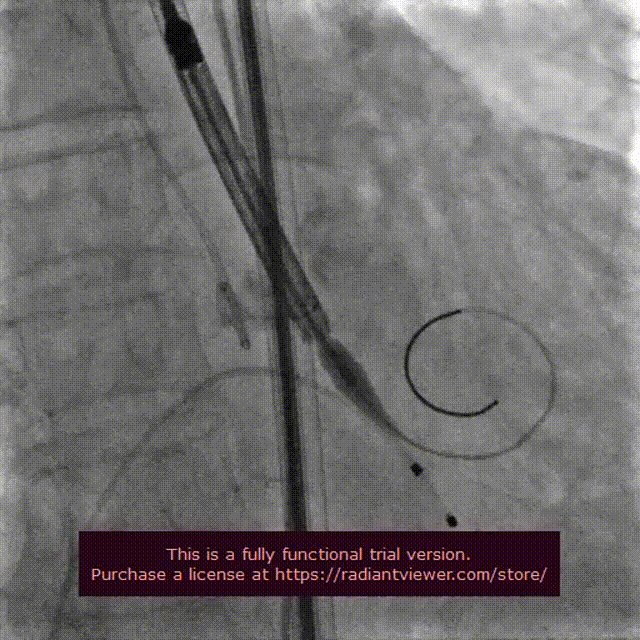

18 mm球囊预扩

输送系统定位

VenusA-Plus®释放过程

18 mm球囊后扩

瓣膜完整形态

术者团队观察到瓣膜形态未能完全伸展,为取得更好治疗效果,后续予以后扩处理。采用18 mm球囊进行后扩后扩,行主动脉造影提示瓣膜置入位置良好、形态完整。